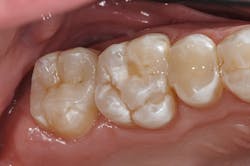

A 27-year-old patient was referred to me due to discomfort associated with dentinal hypersensitivity secondary to erosion on his posterior teeth (figure 1 above: Initial presentation. Note the exposed dentin due to erosion). His former dentist suggested crown lengthening due to inadequate space for full-coverage crowns.

After a thorough evaluation of his clinical presentation, radiographs, and intraoral scan, it was evident that the discomfort was due to exposed dentin. The intraoral scan confirmed there was adequate interocclusal space to restore the eroded tooth structure with a minimally invasive approach (figure 2). All options were reviewed with the patient, and it was mutually agreed upon to address his chief complaint in this manner. Proper isolation is critical for reliable bonding.

Caries lesions were removed and air abrasion was employed to remove impurities on the unprepared tooth surfaces and create increased surface area for bonding. Preparation of the class II carious lesions revealed demineralization on the adjacent tooth structure (figure 3). When lesions such as these are discovered, dentists are often at a crossroads whether to intervene or monitor the area for progression. It is my experience that these early caries lesions can be predictably arrested with resin infiltration (figure 4), and that no intervention usually results in the progression of caries.

In this case, lateral access was achieved by the preparation of the adjacent teeth as part of the proposed treatment plan. Early caries lesions that are noted on radiographs that are not accessible in cases such as this one can be accessed by placing an orthodontic spacer. This patient was restored with direct composite bonding (figure 5) and these restorations have proven to have a favorable long-term outcome (figure 6).